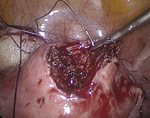

Po wytworzeniu odmy otrzewnej wprowadzono przez pępek trokar 10 mm, a następnie optykę laparoskopu i trokary dodatkowe w podbrzuszu 5 i 10 mm. Pacjentkę ułożono w pozycji Trendelenburga. Uwidoczniono powiększony trzon macicy, ścianę przednią uwypukloną przez mięśniak śródścienny o średnicy około 4-5 cm (ryc. 1), przydatki obustronnie bez zmian. Pozostałe narządy jamy otrzewnej dostępne wizualizacji laparoskopowej były niezmienione.